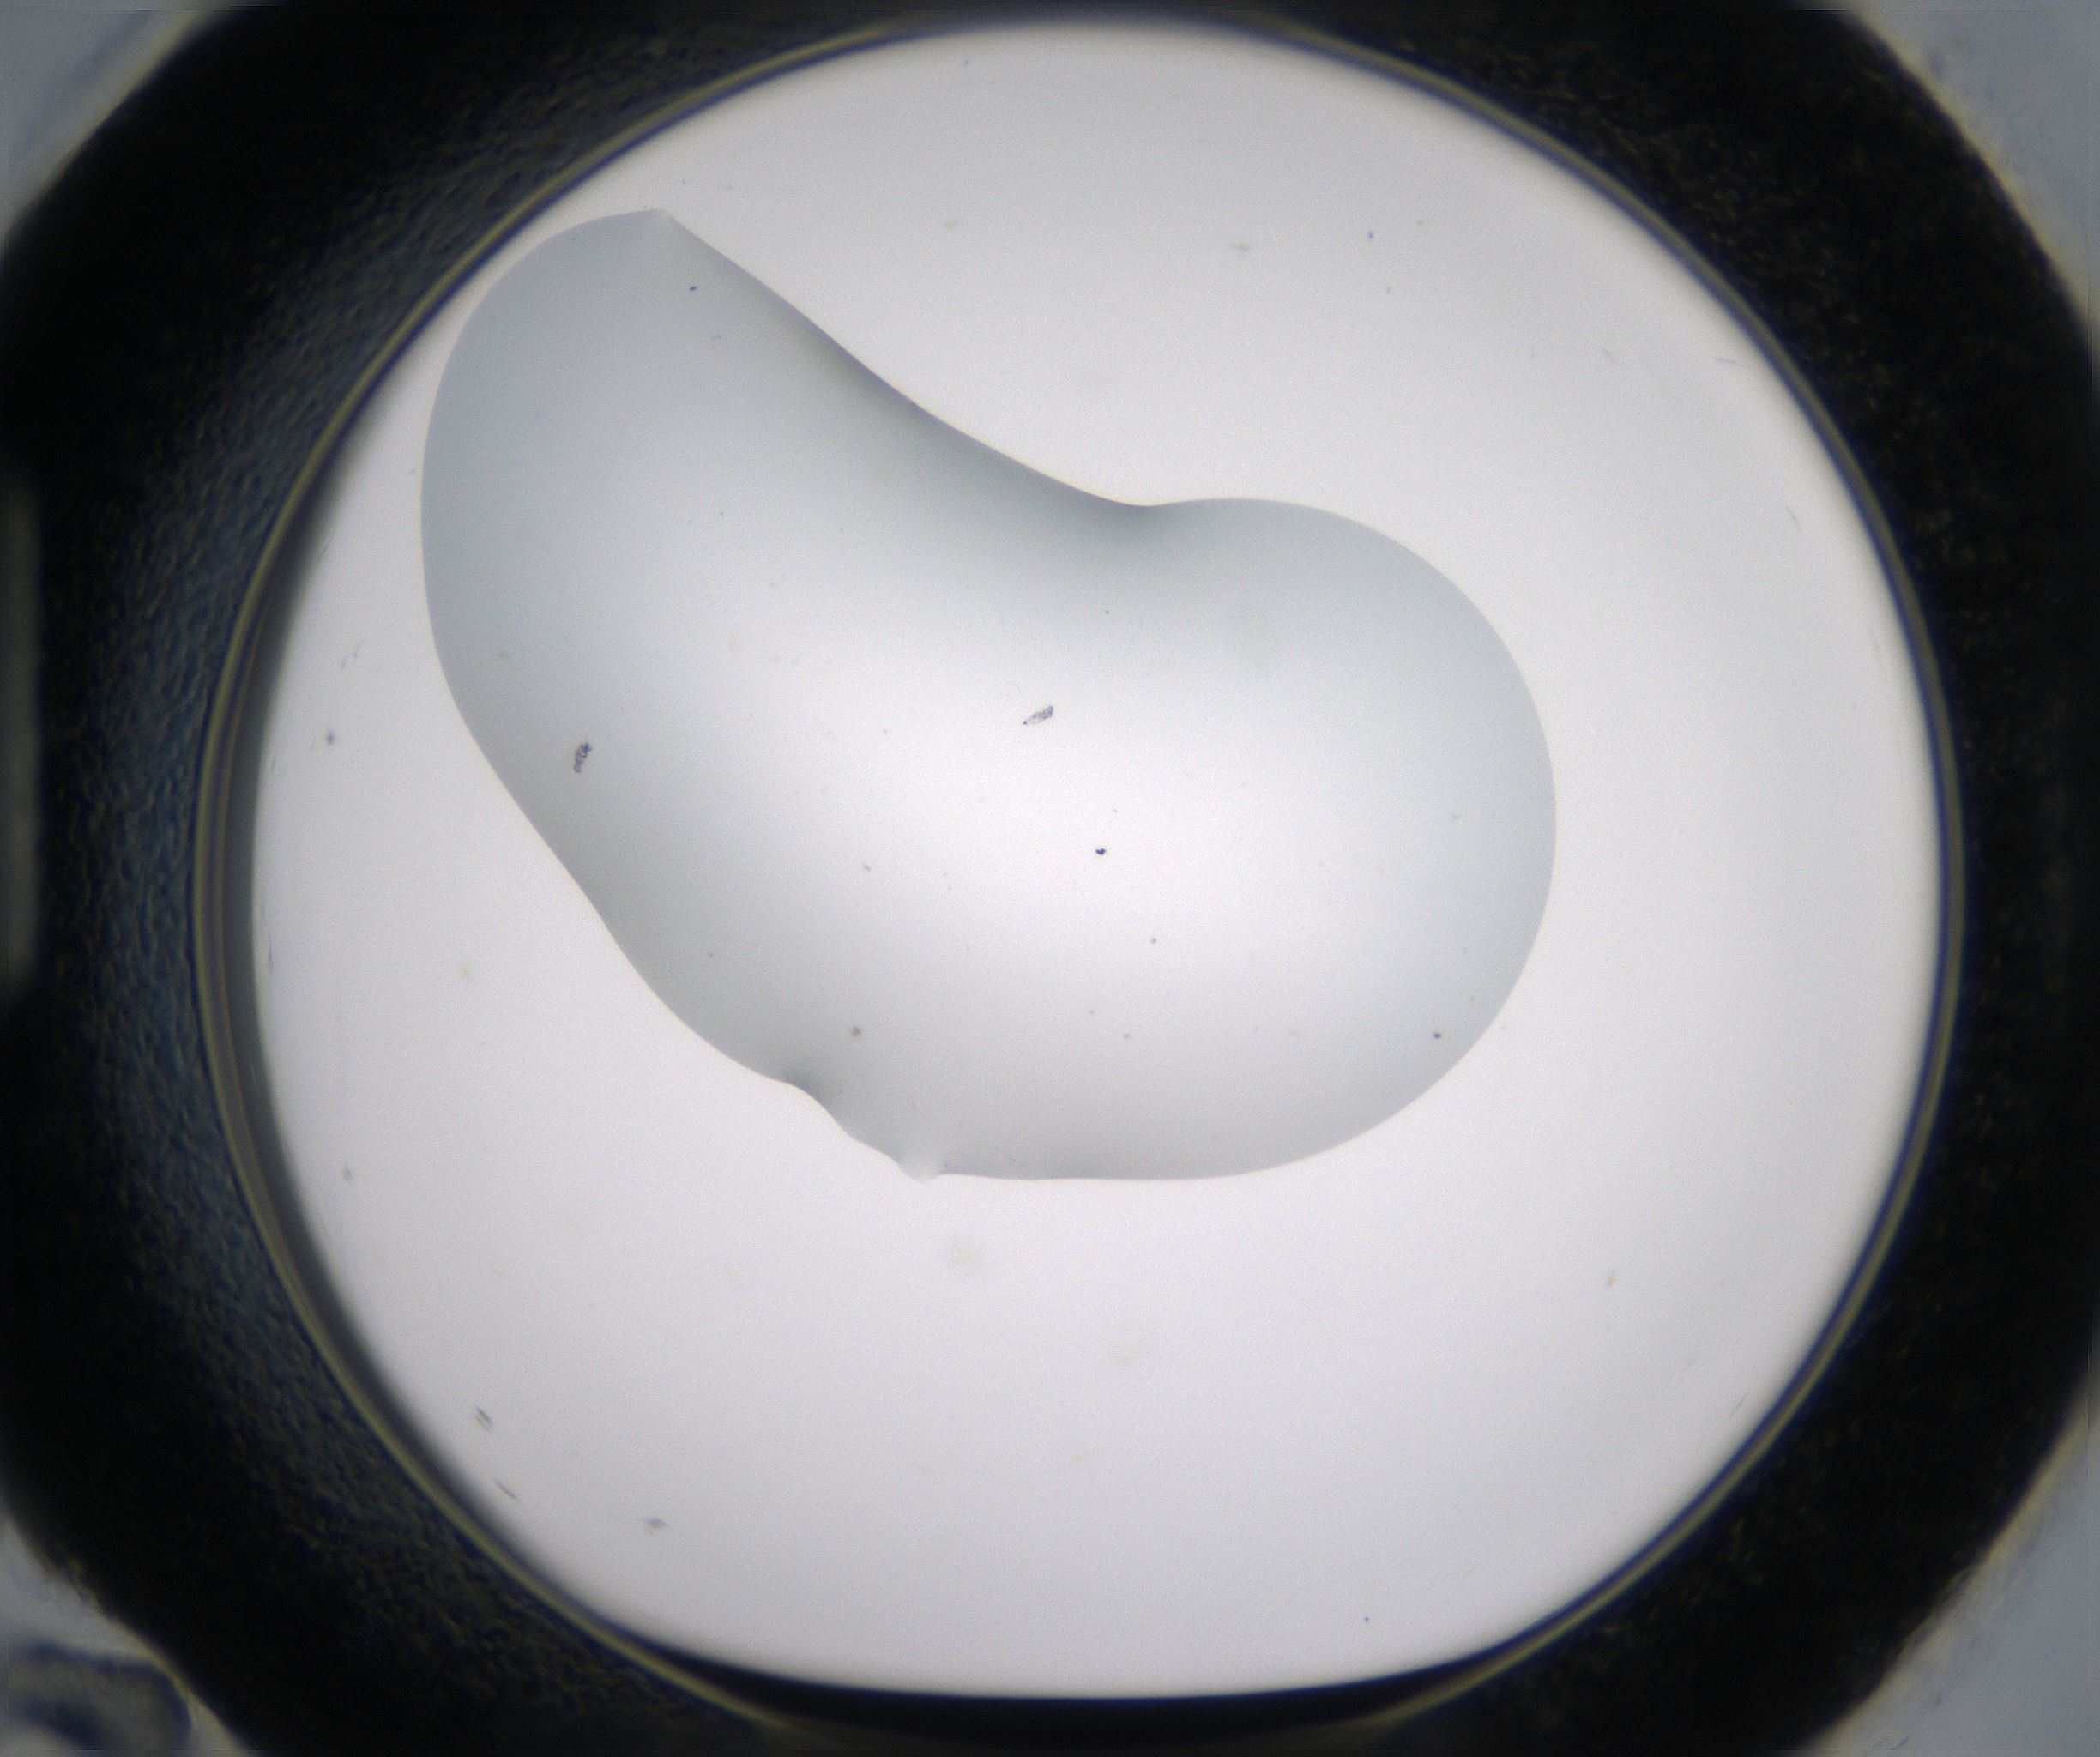

Image 485068

H12_HighResolution_Other_1.jpg